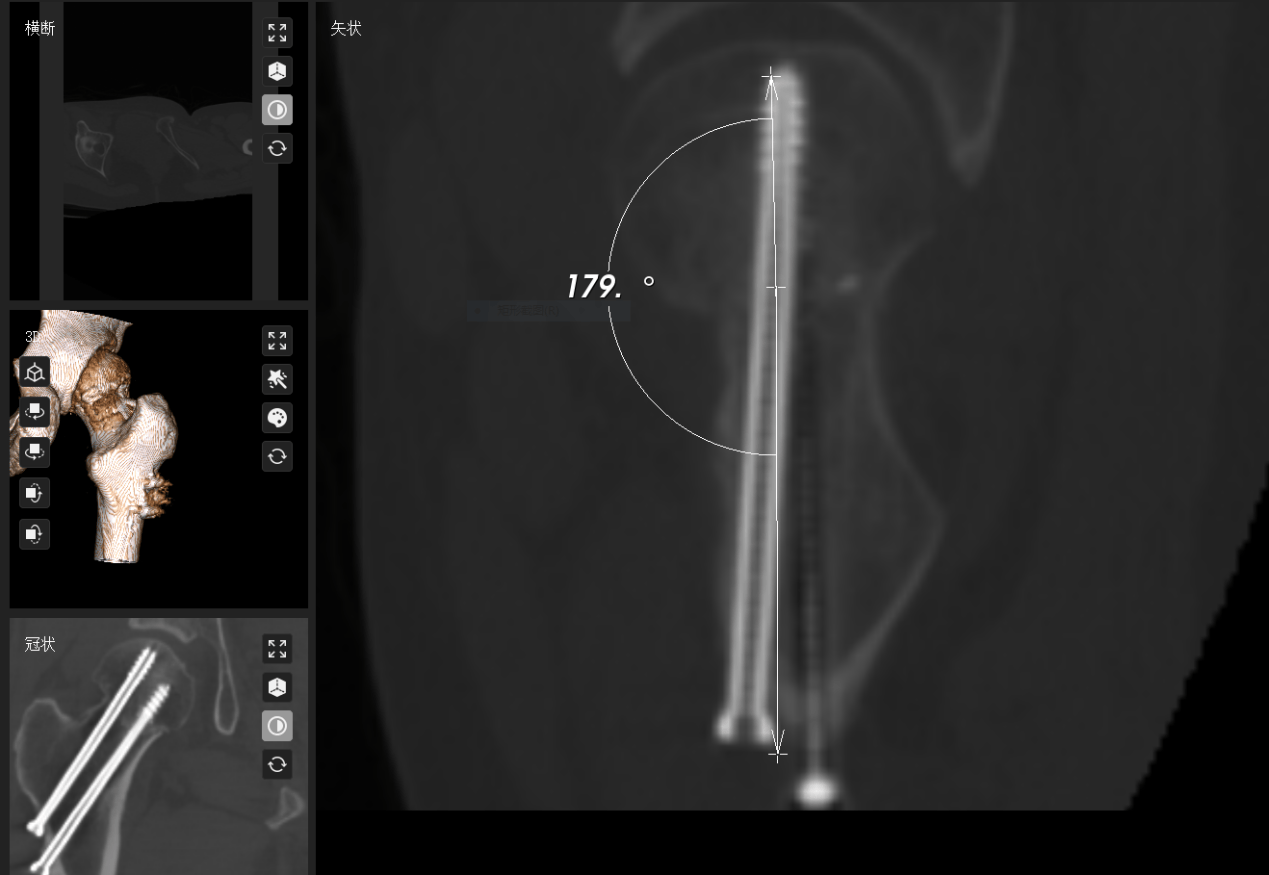

2. 机器人赋能微创固定: 利用先进的骨科机器人及数字化导航技术,叶博士团队实施了空心螺钉内固定术。

技术亮点:

亚毫米级精度(0.8mm): 将螺钉置入精度提升至亚毫米级,显著优于传统手法 ;

最大化保护血供:精准避让脆弱血管,最大限度保护股骨头残存血供,这是降低坏死风险的关键。

3. 动态监测护航: 术后康复并非终点。团队全程动态监测Garden指数,确保其稳定在安全解剖范围内。术后6周结合MRI(如T2WI信号)科学评估股骨头血供变化,为康复计划提供精准依据。